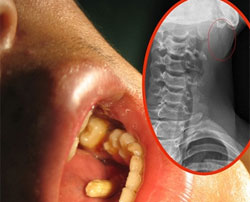

Xiao Wei, sinh viên người Trung Quốc, bị chiếc đũa cắm xuyên qua cằm khi bất cẩn đang ngậm đũa vào miệng thì bị một quả bóng rổ bay trúng người.

Một chiếc đũa đâm vào hàm dưới của sinh viên Xiao Wei.

Xiao Wei cầm xuất cơm trưa và một đôi đũa đi ngang qua sân bóng rổ. Khi điện thoại reo, anh ngậm đôi đũa vào miệng và cho tay vào túi rút điện thoại. Đột ngột, một quả bóng bay vào người anh ta và làm một chiếc đũa xuyên qua hàm dưới.

Chiếc đũa được bác sĩ gắp ra.